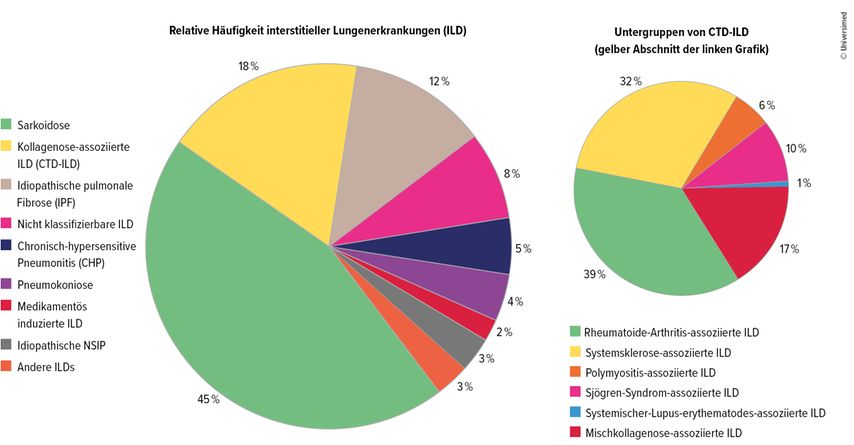

Im Praxisalltag präsentierten sich interstitielle Lungenerkrankungen als diverses Spektrum, das von rein pneumologischen Diagnosen wie der idiopathischen pulmonalen Fibrose (IPF) über Pneumokoniosen bis zur Sarkoidose reiche, erklärte Prof. Dr. Jörg Distler, Düsseldorf, anlässlich seines Vortrag am letztjährigen DGRh-Kongress. Bei einem knappen Fünftel der Betroffenen sei die ILD mit einer rheumatologischen Grunderkrankung assoziiert. Den Großteil machten rheumatoide Arthritis und systemische Sklerose (SSc) aus, Letztere mit einem besonders hohen Anteil progredienter Verläufe. Daneben gebe es die Synthetase- und Mischkollagenose-assoziierten interstitiellen Lungenerkrankungen.1

Abb. 1: Kollagenose-assoziierte ILD (CTD-ILD) machen 18 % der ILD aus und sind in weitere Untergruppen unterteilt. Mod. nach Wijsenbeek M et al.1